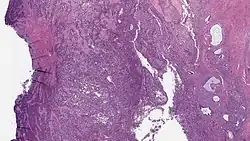

Micrograph of a low-grade endometrial stromal sarcoma. H&E stain.

Low-grade endometrial stromal sarcoma consists of cells resembling normal proliferative phase endometrium, but with infiltration or vascular invasion. These behave less[3] aggressively, sometimes metastasizing, with cancer stage the best predictor of survival. The cells express estrogen/progesterone-receptors.

• Monotonous ovoid cells to spindly cells with minimal cytoplasm.

• Prominent arterioles. Angiolymphatic invasion common.

• Up to 10-15 mitotic figures per 10 HPF in most active areas.

• Tongue-like infiltration between muscle bundles of myometrium.

• May exhibit myxoid, epithelioid and fibrous change.

• May have foam cells or hyalinization in the stroma.